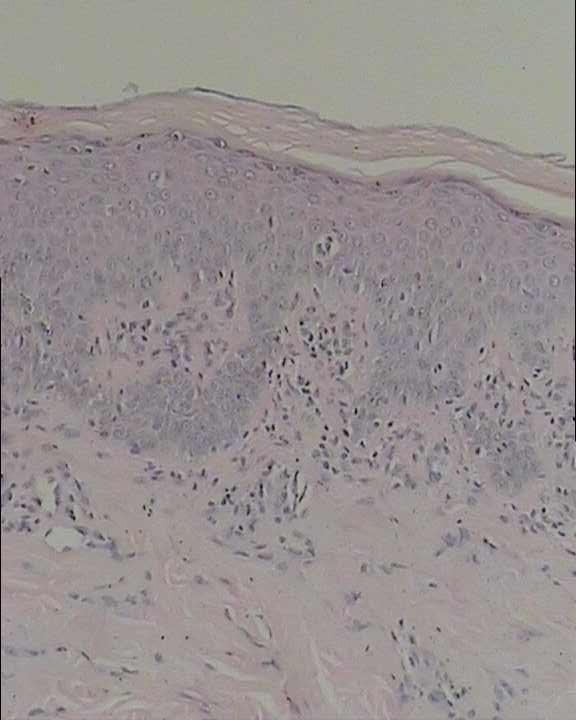

体格检查:系统检查未见异常。皮肤科情况:右侧腰腹部见片状红斑、密集丘疹,抓痕明显,未见糜烂、渗出、水泡(图3)。实验室检查:血分析、尿分析、肝肾功能未见异常;胸片未见异常;真菌检查阴性;体液免疫功能检查正常;ANA、ENA以及dsDNA筛查阴性;右腰部皮疹CT示:棘层轻度灶性海绵水肿,真皮乳头及浅层血管扩张,管周少量炎细胞浸润;取皮疹行组织病理学检查示:皮炎改变(图4)。

诊断:皮炎-带状疱疹后Wolf’s同位反应。予口服扑尔敏、皿治林及外用炉甘石洗剂,8天后皮疹消退。